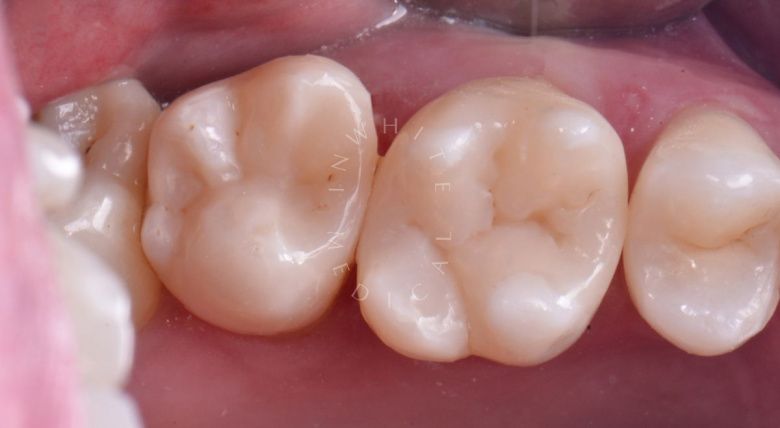

Художественная реставрация формы зубов

Стоматология Москва лучшие клиники. Художественная реставрация формы зубов - после процедуры